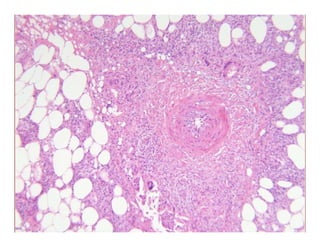

Case 129Case 129Case 129Case 129

Lupus profundusLupus profundusLupus profundusLupus profundus

½ of cases have epidermal and dermal changes of LE½ of cases have epidermal and dermal changes of LE

Lobular panniculitis with prominent lymphocytic infiltrateLobular panniculitis with prominent lymphocytic infiltrateLobular panniculitis with prominent lymphocytic infiltrateLobular panniculitis with prominent lymphocytic infiltrate

–– Characteristic feature:Characteristic feature: paraseptal lymphoid follicles, sometimes withparaseptal lymphoid follicles, sometimes with

germinal centergerminal center

Uncommon in other panniculitidesUncommon in other panniculitides

Late lesions with dystrophic calcificationLate lesions with dystrophic calcification